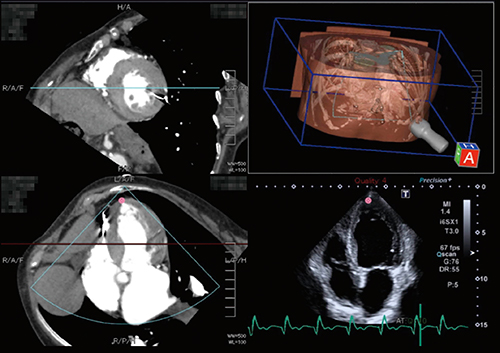

図1は,CTと超音波の4 chamber view(4CV)像をCTの短軸像やプローブ付き3D画像と同時に表示した例である。●は心尖部を指しており,エコー画像がCTの心尖部近傍を描出するとマークが×印に切り替わる。このようにマークを参照することで,CTの画を見ながら適切なエコー断面を描出することができる。

図1 CTと心エコーの4CV像のSmart Fusion表示

(画像ご提供:聖マリアンナ医科大学・出雲昌樹先生)